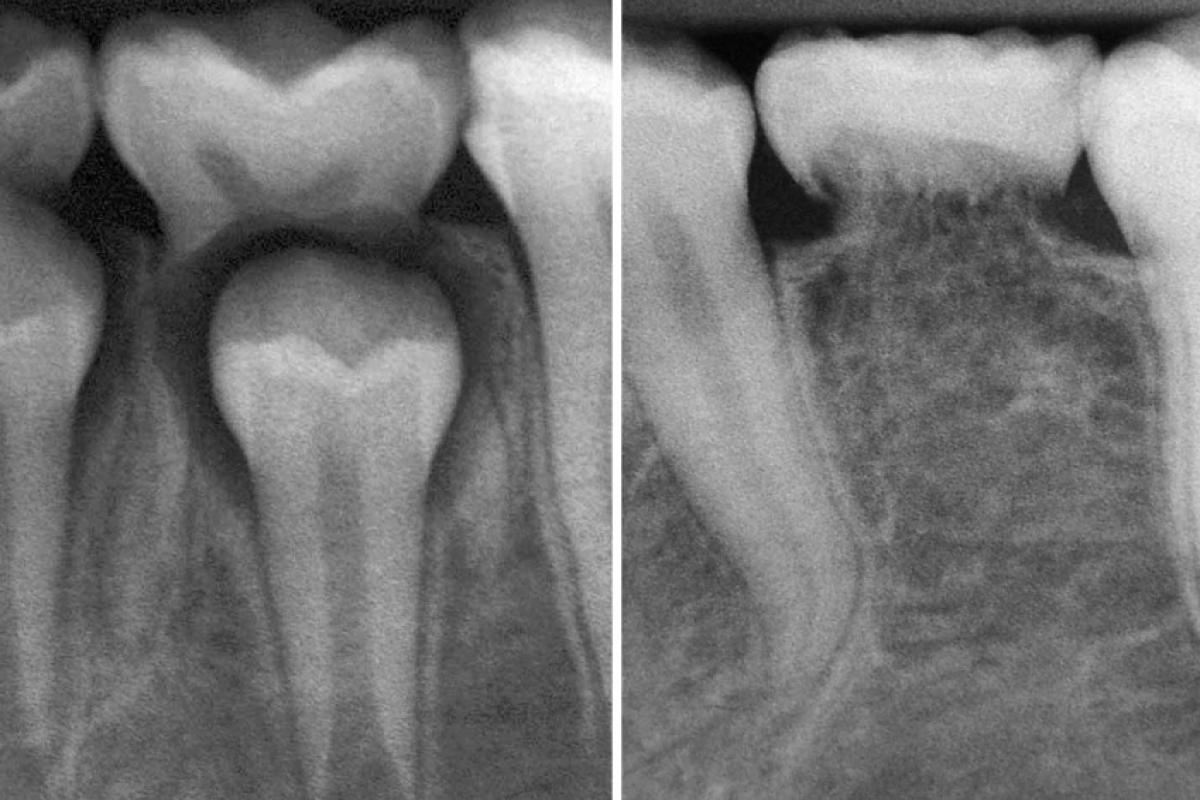

A raiz sumiu: dentes são reabsorvidos

15.03.2025 07h18

COLUNISTA